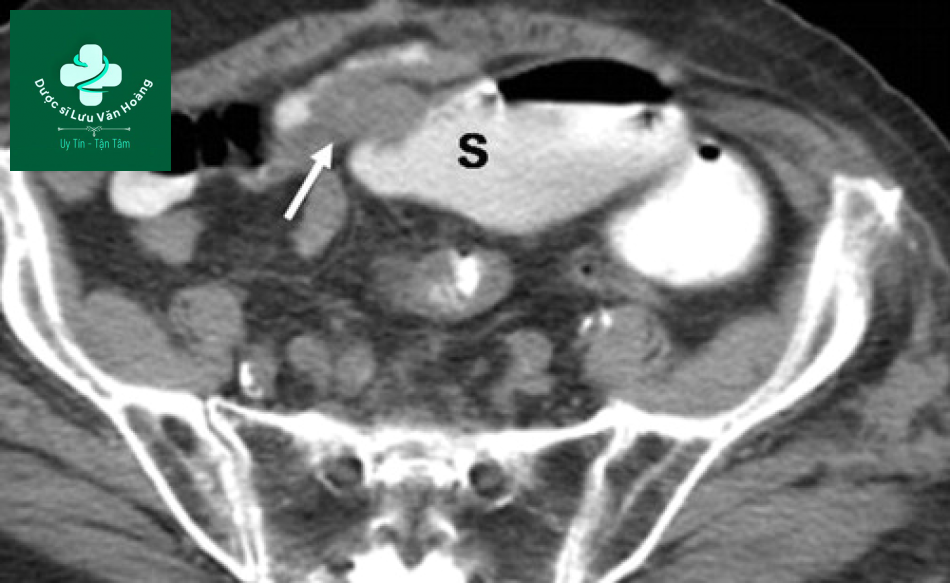

Tắc ruột non ở một trường hợp ung thư biểu mô manh tràng có tổn thương van hồi manh tràng. Hình ảnh CT cho thấy giãn các quai ruột non (S) và hẹp do ung thư ở manh tràng (mũi tên) lan đến đoạn cuối hồi tràng.